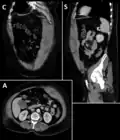

A rectus sheath hematoma is an accumulation of blood in the sheath of the rectus abdominis muscle. It causes abdominal pain with or without a mass.

The hematoma may be caused by either rupture of the epigastric artery or by a muscular tear. Several factors have been identified as predisposing risks for rectus sheath hematoma, including coughing, straining, exercise, hypertension, obesity, previous abdominal surgery, subcutaneous injection, trauma and anticoagulant therapy. With an ageing population and the widespread use of anticoagulant medications, there is evidence that this historically benign condition is becoming more common and more serious.[1] Anticoagulant therapy is used to treat many diseases. However, in the COVID-19 pandemic, anticoagulant therapy was frequently used and therefore the incidence of rectus sheath hematoma increased.[2][3] Given that thrombotic events have been documented in numerous studies, it is advisable to initiate prophylactic and anticoagulant treatment during the early phase of COVID-19 disease.[4]